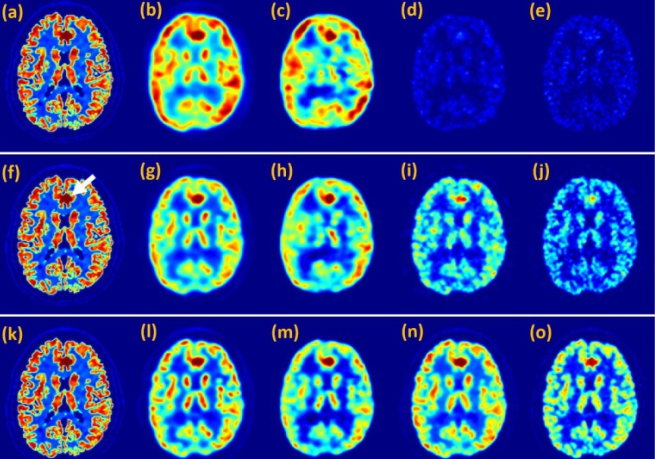

Then, the researchers labeled the screened-out 5MEF with radionuclide 18F through two-step procedure. 18F-5MEF had a high radiochemical yield, less synthesis time and high in vitro stability. MicroPET analysis using 18F-5MEF as PET tracer was performed in healthy BALB/c nude mice for 120 minutes. The results showed that 18F-5MEF showed excellent myocardial accumulation properties for PET imaging with a high initial heart uptake at 5 min post injection and a long retention time in heart within 120 min. 18F-5MEF is a promising mitochondria-targeting PET probe for cardiac diseases.

Besides, the F16 analogues were designed and developed for myocardial dual-modal imaging. 5MEF can provide real-time detection of myocardial viability and myocardial perfusion to guide the operation in heart surgery. The development of 5MEF may inspire more research on the design of myocardia-targeting PET probes based on F16s.